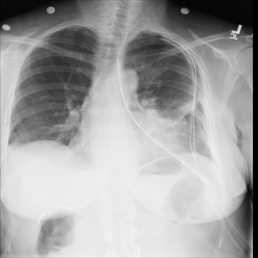

The wide variety of in-distribution and out-of-distribution data in medical imaging makes universal anomaly detection a challenging task. Recently a number of self-supervised methods have been developed that train end-to-end models on healthy data augmented with synthetic anomalies. However, it is difficult to compare these methods as it is not clear whether gains in performance are from the task itself or the training pipeline around it. It is also difficult to assess whether a task generalises well for universal anomaly detection, as they are often only tested on a limited range of anomalies. To assist with this we have developed nnOOD, a framework that adapts nnU-Net to allow for comparison of self-supervised anomaly localisation methods. By isolating the synthetic, self-supervised task from the rest of the training process we perform a more faithful comparison of the tasks, whilst also making the workflow for evaluating over a given dataset quick and easy. Using this we have implemented the current state-of-the-art tasks and evaluated them on a challenging X-ray dataset.

翻译:医疗成像中分布和分配外数据的多样性使得普遍异常现象的检测是一项艰巨的任务。最近,开发了一些自我监督的方法,对健康数据与合成异常现象相结合的健康数据终端到终端模型进行培训。然而,很难比较这些方法,因为尚不清楚绩效的收益是来自任务本身还是来自围绕任务的培训管道。还难以评估一项任务是否有利于普遍异常现象的检测,因为这些任务往往仅在有限的一系列异常现象上进行测试。为了协助这项工作,我们开发了NNNOOD, 该框架调整了NNU-Net, 以便能够比较自我监督的异常地方化方法。通过将合成的、自我监督的任务与我们完成的其余培训过程分开,使我们对任务进行更加忠实的比较,同时使评估特定数据集的工作流程迅速和容易。我们利用这一方法执行了目前最先进的任务,并在具有挑战性的X光数据集上评估了这些任务。